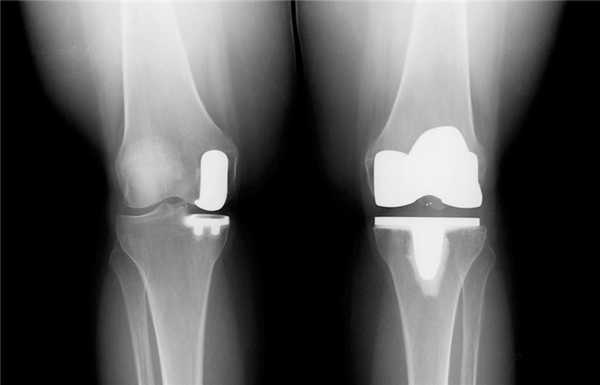

Две техники операции у одного пациента.

Одномыщелковая замена сустава на рентгене.

Сравнение двух типов операций.